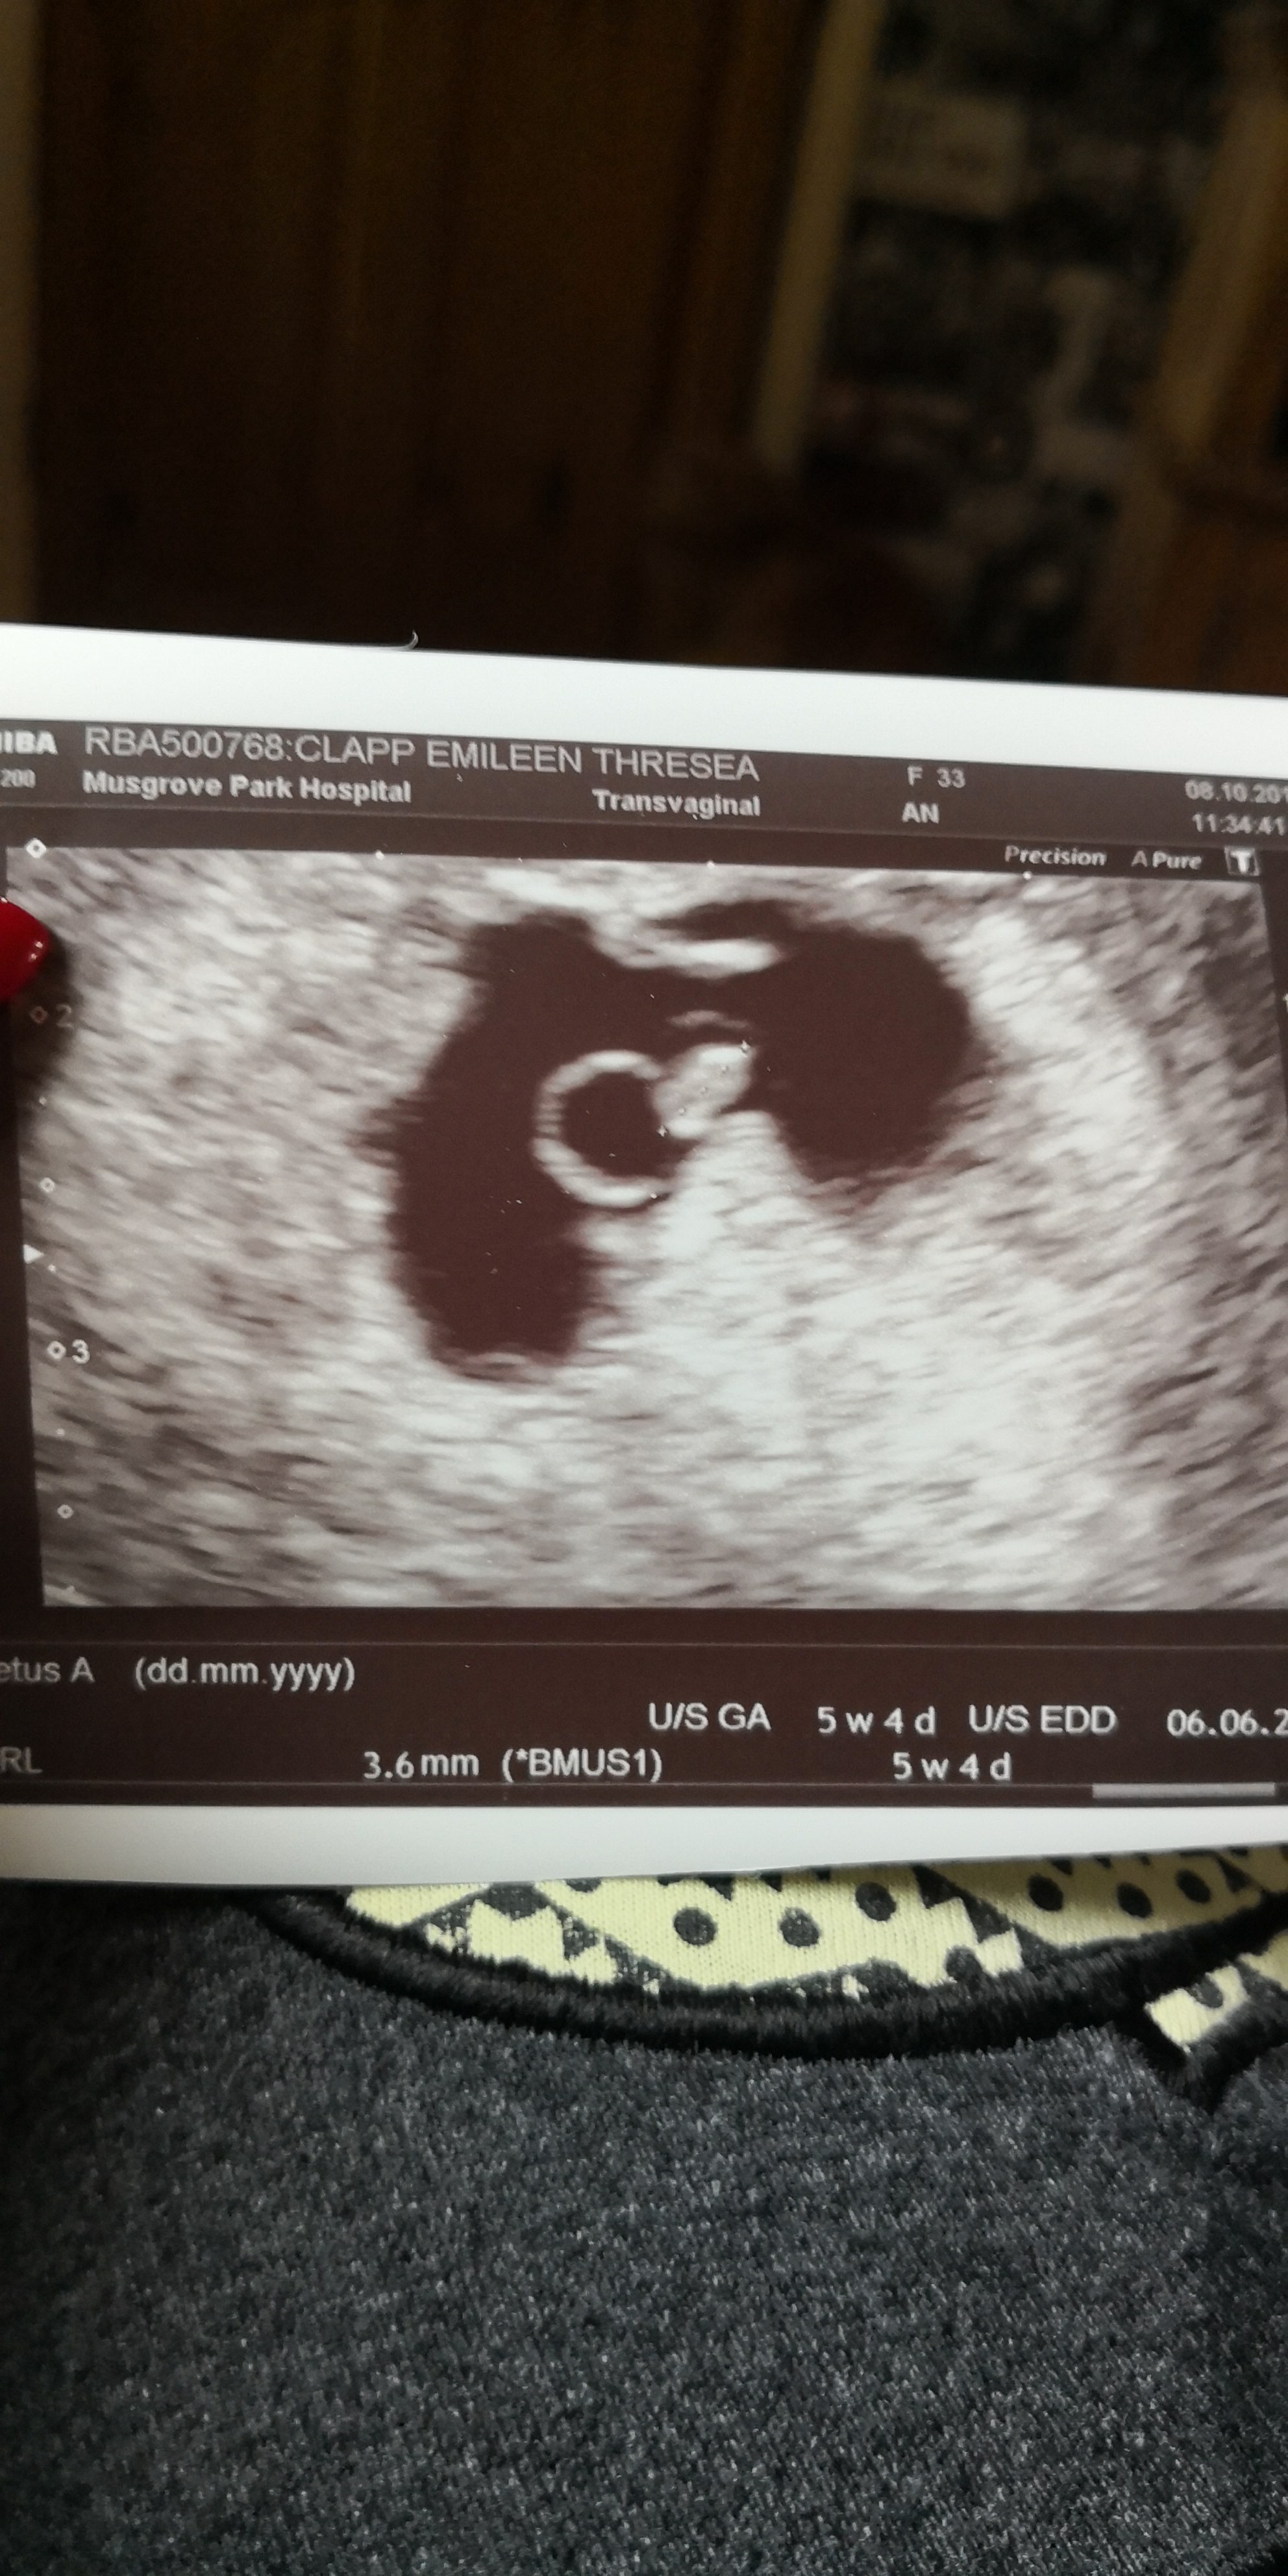

We’re another two weeks into the pregnancy, Paisley had recovered from the hand, foot and mouth, her condition is under control now that we have the right stuff to treat her, I had managed to avoid getting a tempature! All in all things were looking good! We were so excited about the baby, we named the bump Boris, we kept talking about him Infront of the kids, luckily they thought it was someone we know and not our bump name. I had a massive wobble the night before our 6week scan, I told Nathan not to bother coming to the scan, I said they would’t find anything anyway. I don’t know what it was but something just didn’t feel right! My boobs didn’t hurt – I’m sure they hurt at my 6week scans with the girls! I told a friend about the baby, I told her things felt different and I’m scared, she thought the baby was a boy and that’s why it felt different and that I was panicking because the two I lost before the girls. It was a difficult year last year, my eldest should have been 16 on the day we turned 12 weeks and it was 10 years ago that year that I lost the ectopic pregnancy. That thrown in with my poor mental health during my pregnancy with Paisley and all the extra pregnancy hormones = I was a massive scared mess! Anyway we went to our scan feeling calmer than I had the night before, they asked the usual questions, about my previous pregnancies, they asked how the ectopic was treated, I responded “like cancer” and broke down into tears! I gathered myself and got on the bed, the lady was so kind, she told us straight away that the baby was ok and in my womb! I cried again, I was so relieved. She turned the screen and talked us through the scan, we were measuring a bit earlier than we thought we were but that didn’t count at the early scans so we didn’t bother ourselves with it. Then she told us there was a slight abnormality with the shape of the sac, it might be nothing but they needed us to come back in two weeks to check how the baby’s growing and that if I experienced and bleeding I was to go straight in. The baby’s sac was irregular and that may have caused problems meaning the baby wouldn’t grow and we would lose it. We booked our appointment for two weeks time and were told to make a midwife appointment so they could start supporting me with my mental health.

After a long and emotional two weeks we are finally at our 8 week scan, I am terrified I feel sure that there’s something wrong, it’s the same lady scanning us. She didn’t wait around, she could see how anxious I was. I felt sick (more than the usual morning sickness) and then there it was, our beautiful baby with the beginnings of little limbs and a strong heartbeat, measuring at 8 weeks and 3 days. I was amazed, this sudden rush of relief. She told us that the baby was growing well and the sac was much more regular and was no longer cause for concern. We didn’t need to come back to this clinic again and I would be seen for my 12 week scan as normal, I was slightly told off as I still hadn’t informed a midwife of my pregnancy, she was concerned about my mental health. I promised I would go straight home and book an appointment, I just couldn’t face it as I was sure we would get bad news today. I finally felt like this baby was going to happen, complete excitement and joy!